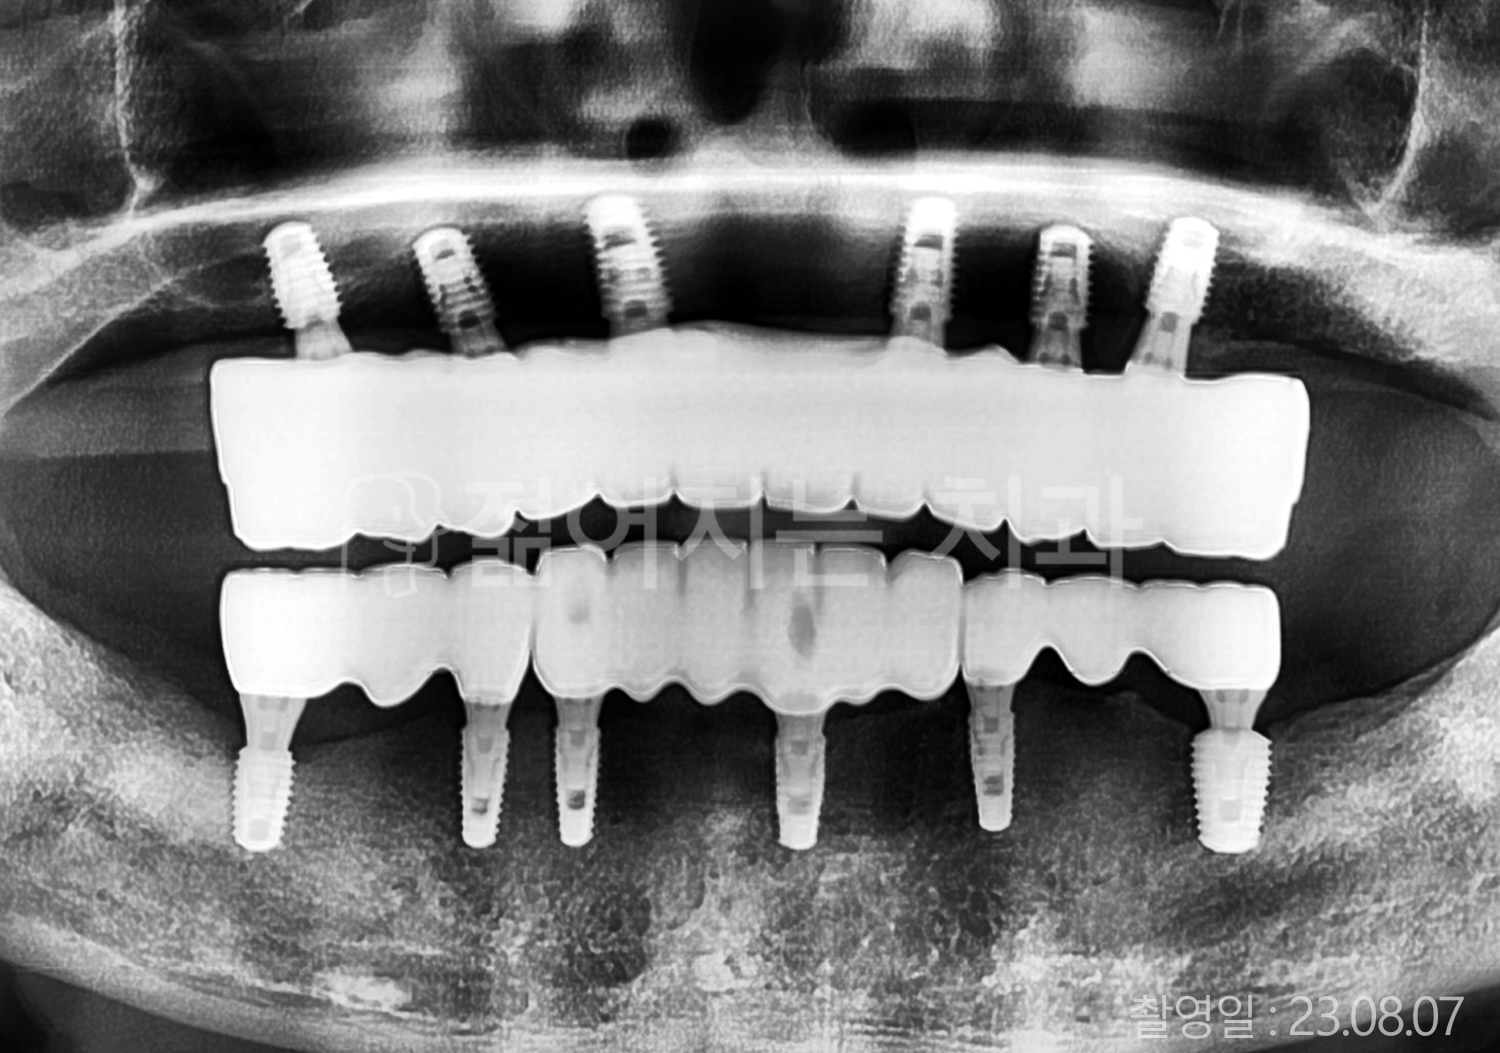

• 40대 전체치아 10개 이상 임플란트

• 70대 당뇨 전체치아 10개 이상 임플란트

• 60대 전체치아 10개 이상 임플란트

• 60대 고혈압, 당뇨, 고지혈증 전체치아 10개 이상 임플란트

• 50대 전체치아 10개 이상 임플란트

• 70대 고혈압, 당뇨 전체치아 10개 이상 임플란트

• 60대 고혈압 전체치아 10개 이상 임플란트

• 50대 고혈압, 당뇨, 고지혈증 전체치아 10개 이상 임플란트

• 60대 고혈압, 고지혈증 전체치아 10개 이상 임플란트